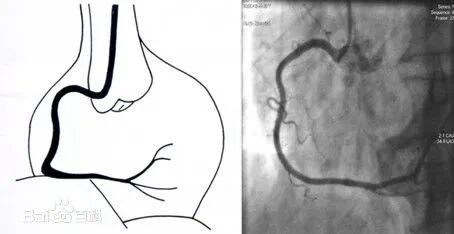

左前斜:RCA呈“C”型,观察RCA开口、起始部至后降支

-

后前位+头位:RCA呈“L”型,观察RCA远端分支及其开口情况